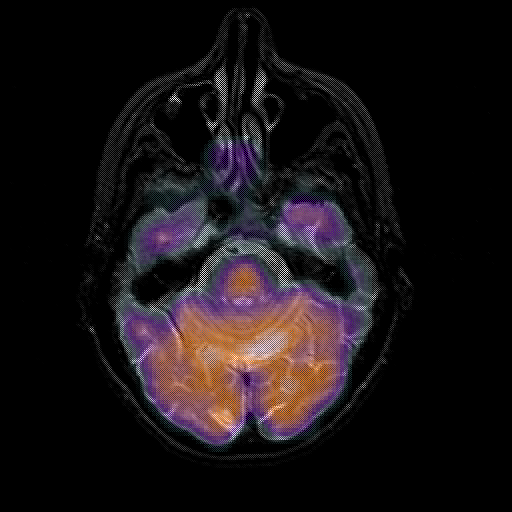

overlay 1: Slice 16

Slice 16